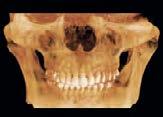

Con los estudios realizados se confirmó clase III dental, depresión del tercio medio en la cara, observándose una discrepancia en el tamaño del maxilar contra la mandíbula y ausencia del OD 63, radiográficamente el OD 23 aún sin erupcionar (Figura 1).